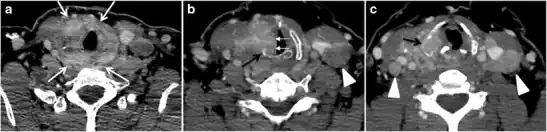

Fig. 6. A 61-year-old female patient with locally aggressive PTC. an Enhanced axial CT scan of the neck demonstrates a heterogeneous infiltrative thyroid mass. This mass diffusely involves the entire gland and circumferentially encases the trachea with involvement of bilateral tracheoesophageal grooves (white arrows). b, c Additional axial cranial images show right cricoid cartilage destruction (black arrows in b), right thyroid cartilage destruction (black arrow in c), right vocal cord paralysis (white arrows in b), and bilateral cervical lymphadenopathy (arrowheads).[1]

Fig. 11. Thyroid non-Hodgkin's large B-cell lymphoma in a 66-year-old female patient. an Axial enhanced neck CT scan demonstrates left thyroid lobe and isthmus homogeneously hypodense and minimally enhancing mass (white arrows). This lesion invades the prevertebral muscles (black arrows). Note the multiple enlarged level V lymph nodes (white arrowheads). b Post-treatment image shows significant reduction in size and mass effect of the left thyroid infiltrative mass, with almost complete resolution of the left cervical lymphadenopathy.[1] -

Fig. 12. Diffuse thyroid large B-cell lymphoma in a 79-year-old female patient. an Axial enhanced neck CT scan demonstrates a homogeneously hypodense and minimally enhancing large right thyroid solid mass (long white arrow) extending into the thyroid isthmus. It is encasing the right carotid artery (short white arrow) and displacing of the trachea and oesophagus to the left side.[1]